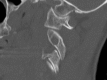

Fractures of the second cervical vertebra (C2, axis) are common in adult spine surgery. Those fractures occurring in younger adult patients are often associated with high-energy mechanism trauma, resulting in a "Hangman's Fracture." Management of these fractures is often successful with nonoperative means, though surgery may be needed in those fractures with greater displacement and injury to the C2-C3 disc. Older patients are more likely to sustain fractures of the odontoid process. The evidence supporting surgical management of these fractures is evolving, as there may be a mortality benefit to surgery. Regardless of treatment, longer-term mortality rates are high in this patient population, which should be discussed with the patient and family at the time of injury. Pediatric patients may suffer fractures of the axis, though differentiation of normal and pathologic findings is necessary and more difficult with the skeletally immature spine.